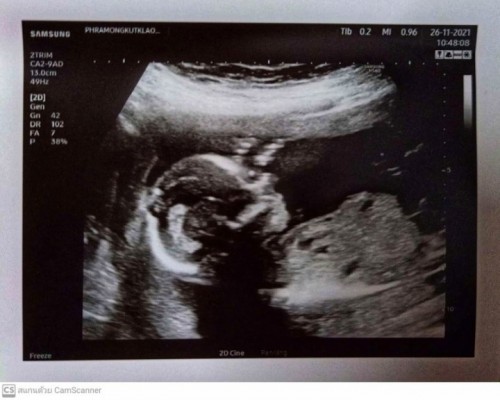

ไม่ว่านู๋จะเป็นผู้หญิงหรือผู้ชายแม่ก็รักนะคะ ( 19+2week ) ทีมเมษาคะ

- จมูกนู๋ปังมากคะลูกถูกใจแม่หล๊ายหลาย - แม่ๆมาโชว์ฟิล์มอัลตร้าซาวด์กันคะบ้านนี้ได้ลูกชายจมูกโด่งมากคะ #คุณหมอแจ้งว่าได้ผู้ชาย #แต่ส่วนตัวอยากได้ผู้หญิงเพราะ3ท้องที่ผ่านมาเป็นผู้ชาย #ลูกชายคนที่4

ไม่ว่าลูกจะเป็นผู้หญิงหรือผู้ชายแม่ก็รักนู๋นะคะลูก???